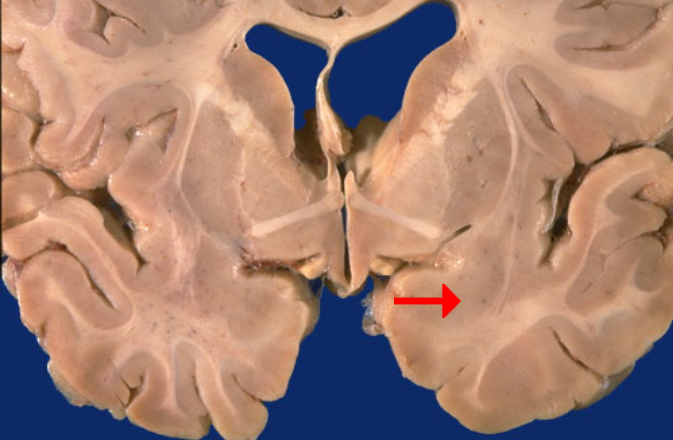

Label this brain structure

Globus pallidus